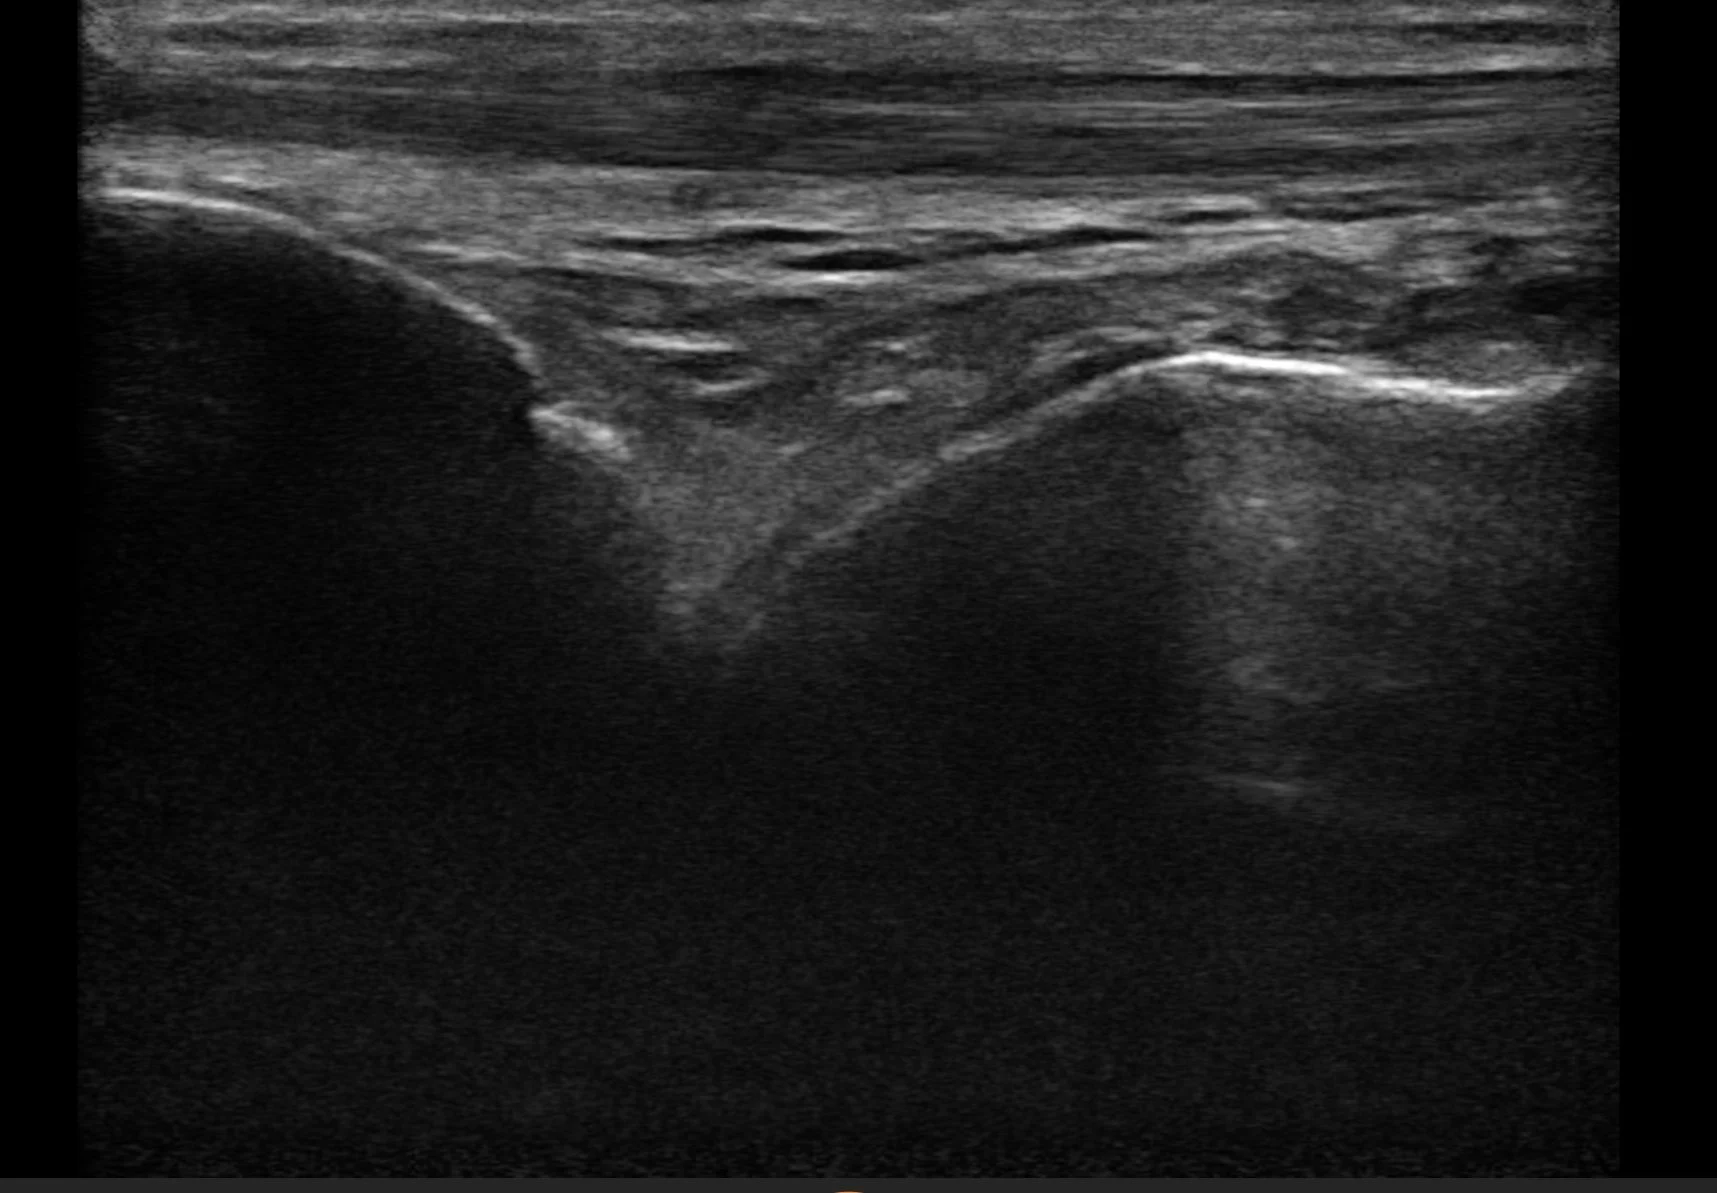

Ultrasound imaging uses sound waves to create real-time visualisations of soft tissues, muscles, ligaments, and joints. This non-invasive and painless method allows us to diagnose various conditions with exceptional accuracy.

• Precise Diagnosis: Efficiently identify issues such as plantar fasciitis, tendon injuries, and soft tissue damage.

If you suffer from chronic foot or ankle pain, swelling, or reduced mobility, our ultrasound imaging service could provide the clarity and answers you need.